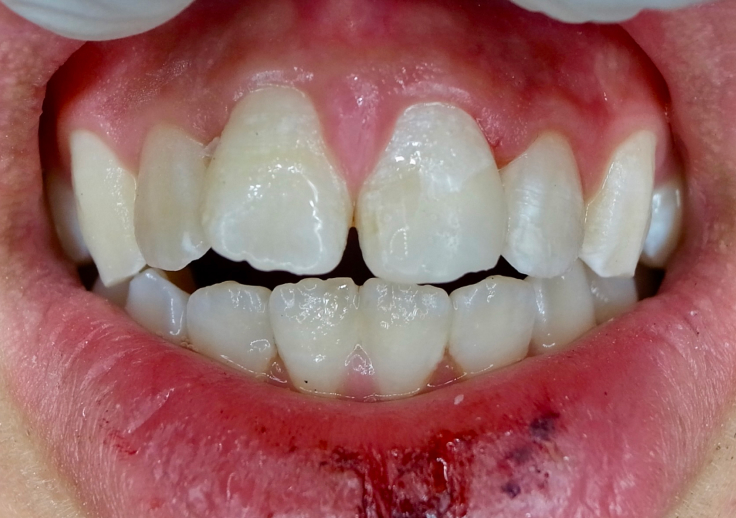

Before

After

After 歯が欠けた・折れた場合の治療は、